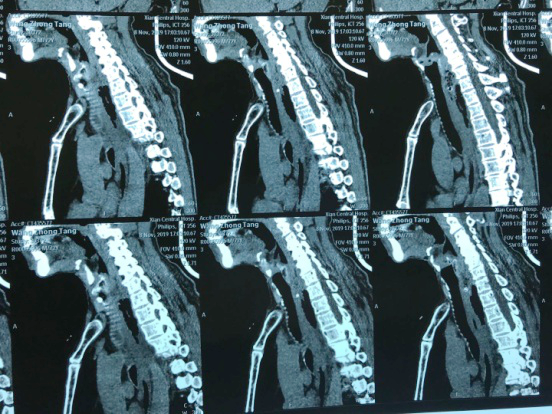

“大夫,快,我这人卡枣核5天没吃饭了,县医院说枣核又往下掉了”,2019118日下午,一位72岁老人在一群家属的搀扶下来到六合彩生肖 耳鼻喉科门诊,门诊医师刘飞接诊患者询问病史,原来老人在村里“坐席”不慎将枣核误吞,在村卫生室、县城医院等多家医疗机构就诊,未能取出枣核,考虑枣核位置不断下移,建议转上级医院。至此患者因咽痛无法下咽已经5天滴水未进。患者既往糖尿病、冠心病,且未规范药物治疗,基础条件很差。考虑患者病情危重,予以迅速办理入院。权博源主任医师和尹黎波主治医师详细询问病史及查体后,为患者急查血:白细胞22,血糖、血酮、尿酮高,凝血象报危急值。患者食道异物食道穿孔合并严重感染,长期饥饿合并高血糖,手术风险很大。权博源主任医师亲自为患者制定治疗方案,立即抗感染、补液治疗,请内分泌科协助降糖降酮治疗,同时复查CT确定枣核现在位置,指标控制后立即手术。晚上10点,在麻醉科、手术室紧张有序的配合下,终于将枣核和覆盖在上方的鸡蛋样异物取出,术后患者平稳返回病房。